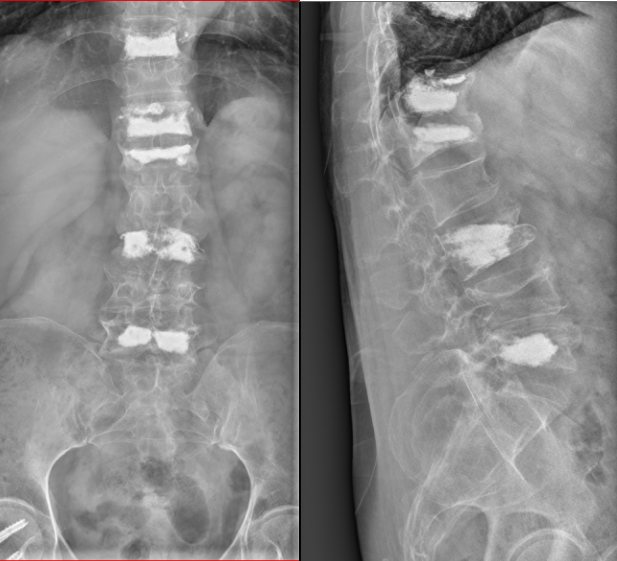

按照术前计划,谢某首先接受了腰麻下的股骨颈骨折闭合复位空心钉内固定术。手术过程非常顺利,四十分钟便完成了。术后观察期间,医生为她进行了精心的后续治疗。病情稳定后,又为谢某做了两次腰椎骨折的微创手术。每次手术过程都是同样短暂,但效果极佳。局部麻醉的运用,谢某在手术过程中几乎感觉不到任何痛苦。

虽然术后的X光片看起来令人触目惊心,但实际上,这些复杂的手术都是通过微小的切口完成的。最大的伤口只有1公分大小,最多只需缝合一针。而背部的切口更是小得如同“小眼”一般,无需缝合和拆线。大约一周后,谢某就可以自行移除纱布了。